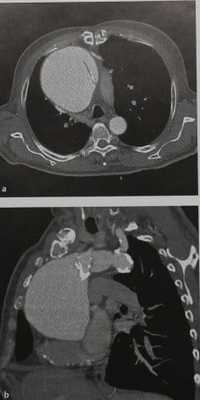

Аневризма восходящей аорты у мужчины 62 лет. На КТ видна крупная аневризма восходящей аорты с лоскутом разорвавшейся интимы.